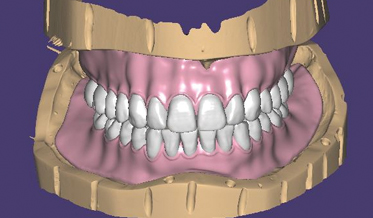

The Reverse Scan Body Protocol: Completing the Digital Workflow

Digital Workflow as an Aid to Complex Multidiscipline Dental Treatment for Improved Esthetics

Fred A. Puccio, DDS; and Gregori M. Kurtzman, DDS